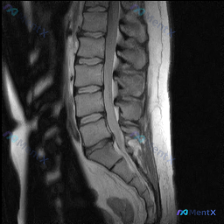

网上看到一份病例资料,用户标注提示是「脊柱侧弯」,但只给了一张腰椎MRI T2序列矢状位的图像和描述。 先把影像里的几个关键点列出来: - L4/5、L5/S1椎间盘信号明显减低(黑盘征),后缘突出,硬膜囊前缘受压 - 局部椎管矢状径变窄,黄韧带可能有肥厚 - 椎体序列生理曲度存在,未见明显楔形变或...

整理网上看到的一份影像讨论资料: 有人拿着一张腰椎T2加权矢状位MRI问是不是有脊柱侧弯。 先不直接说结论,先把这份影像的可见表现列出来,大家觉得第一时间应该关注什么? 影像可见表现(仅基于矢状位): 1. 腰椎多个节段(尤其是L3/L4、L4/L5、L5/S1)椎间盘T2信号减低,椎间隙高度有改变...

整理了一份腰椎影像资料,用户一开始问的是“这张图能看到脊柱侧弯吗?”。先说明一下,只有这份腰椎MRI T2加权矢状位序列。 先说说图里明确能看到的: 1. 多个腰椎椎间盘信号普遍减低,考虑广泛脱水退变; 2. L4/L5、L5/S1这些下腰段椎间盘后缘向椎管内突; 3. L3/L4、L4/L5、L5...